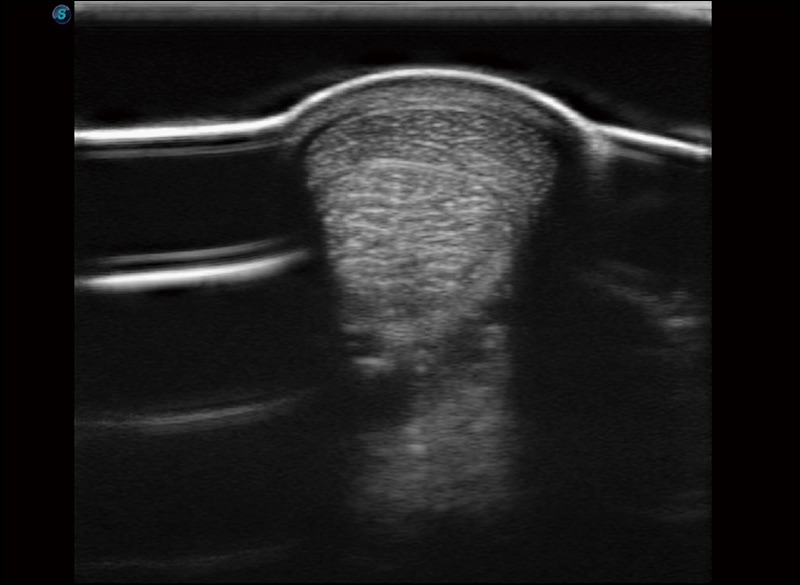

擴(kuò)展成像

支持線陣和凸陣探頭,一鍵操作即可獲得更寬的圖像視野

實(shí)時(shí)寬景成像

可實(shí)時(shí)觀察感興趣區(qū)域和病變位置